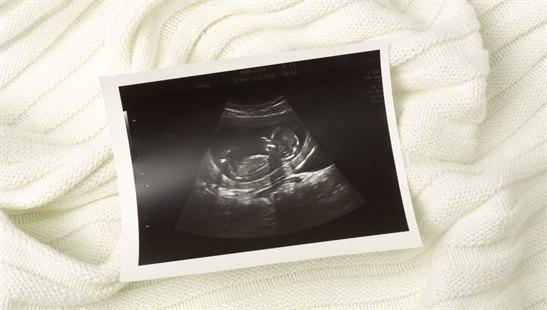

Forestillinger om hvordan et barn blir til i mors mage, har alltid vekket stor undring og begeistring. Med utgangspunkt i én celle dannes et miniatyrmenneske i løpet av drøyt to måneder.

Moderne ultralydteknologi har bidratt til mye av den kunnskapen vi har i dag på dette området. Men vi har fremdeles mye å lære om det som mange kaller et mirakel.